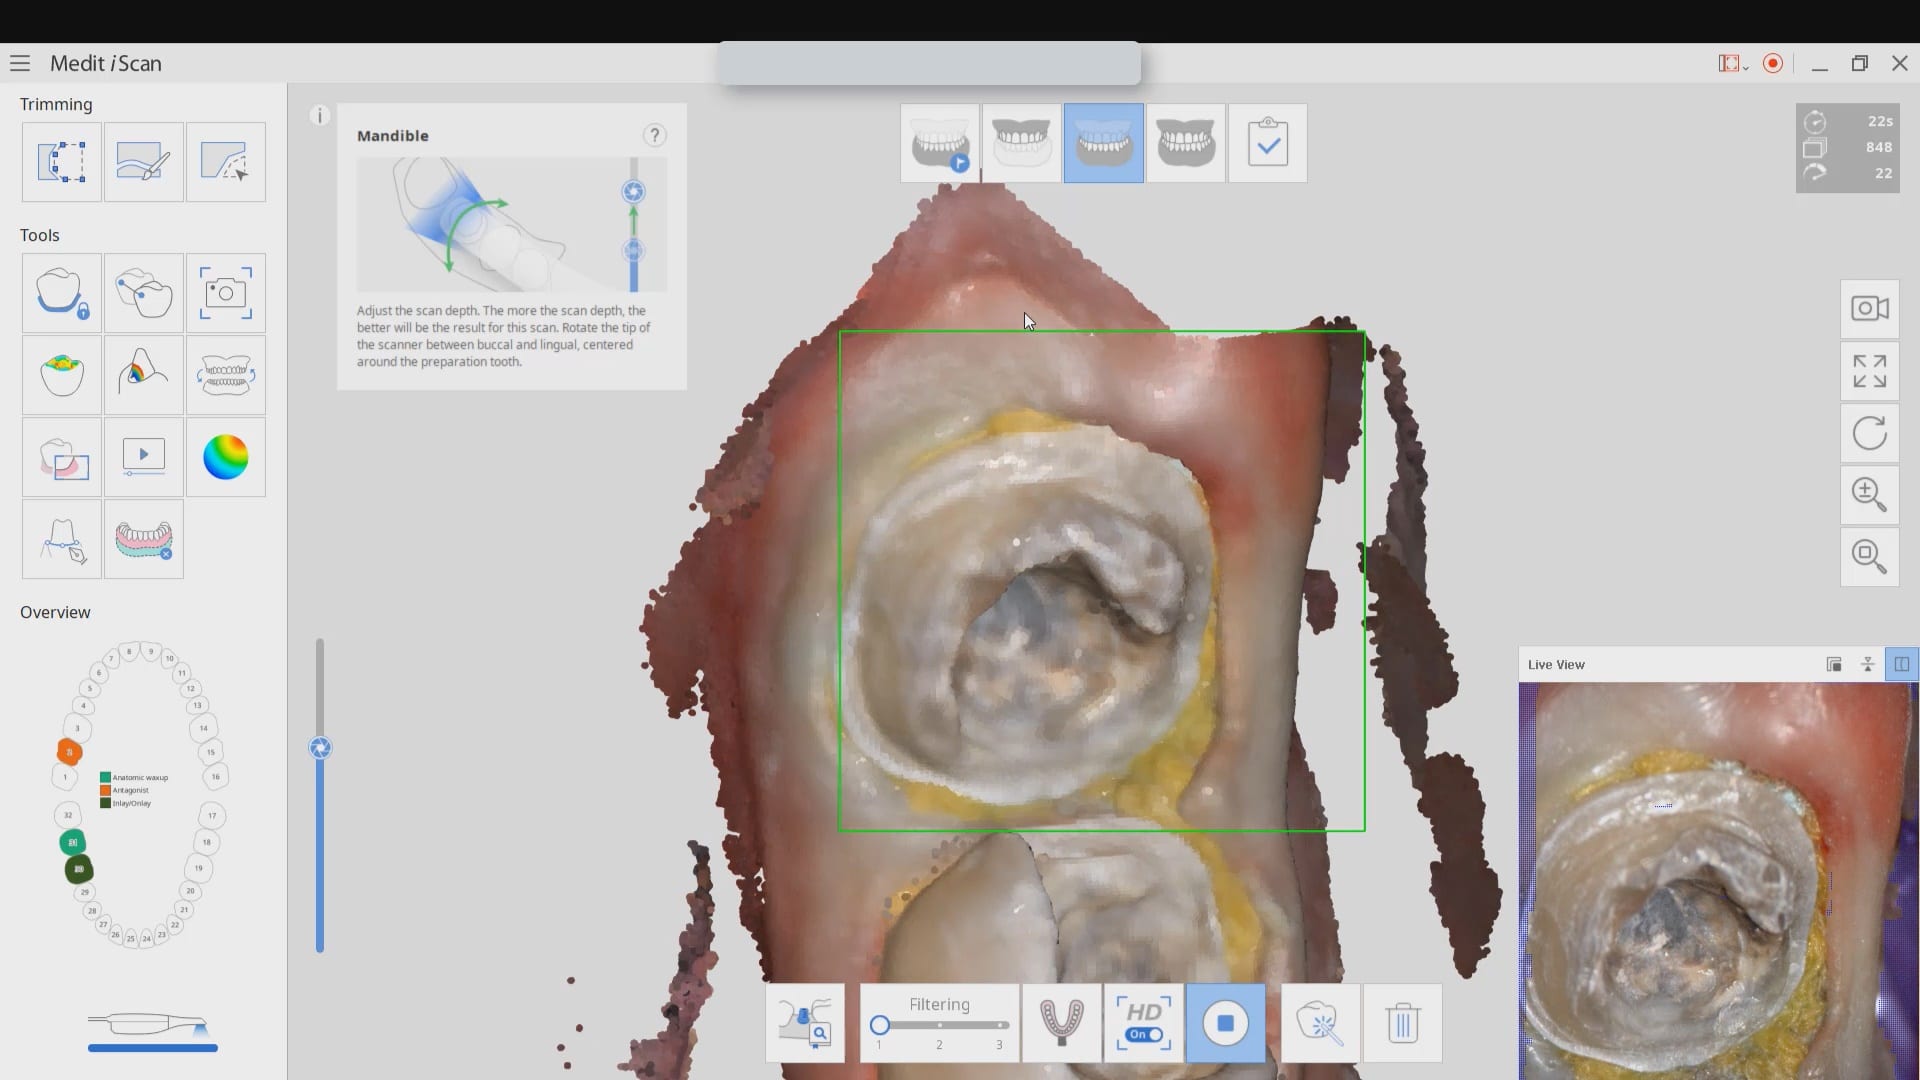

November 19, 2019Have you ever compared the milled product with the designed restoration? We scanned with the medit i500, designed with exocad and milled with coritec. after try-in, we scanned the restoration […]